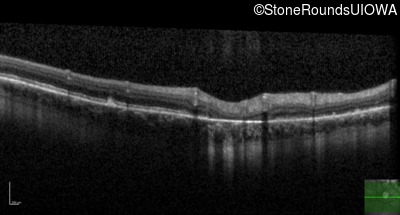

Optical Coherence Tomography - Right - 20/20 -2 sc

Exemplar / OCT Stack

Optical Coherence Tomography - Left - 20/30 +1 sc